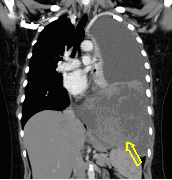

3a: Round shadow: multiple lung metastasis. Chest radiograph (PA)

3b: Multiple lung metastasis, CT lung window (axial, coronal reformat)

3c, coronal reformat

70 year old man, colon tumor.

Radiograph: Bilateral extensive, confluating patchy-nodular shadowing with diffuse reticular pattern. The diaphragm contour is partially blurry bilaterally: lymphangiosis carcinomatosa.

CT: Numerous 1-6 cm round and irregular, lobulated-spiculated contrast enhancing lesions in both lungs, everywhere sporadically.